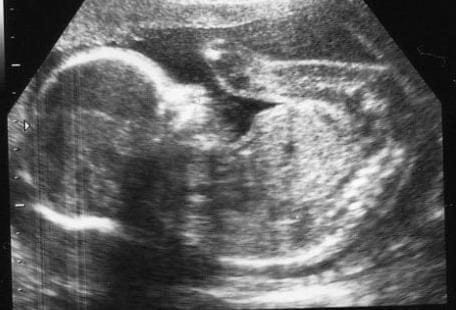

Ashley Bridges ha 24 anni, è americana, e malata di tumore osseo. Una delle forme di cancro più terribili e dolorose. Ashley, che ha due occhi grandi da bambina, è sposata, ha due figli, Braiden e Paisley. Il più grande ha sei anni, e ha capito benissimo il dramma che si vive a casa. Ha capito che la mamma sta per volare via, e vuole andarsene con lei. Paisley non comprende, ha soltanto due mesi. Nata leggermente prematura, è il raggio di sole della sua nera notte di dolore e paura. Lo è ogni figlio per ogni madre. Lo è ogni figlio per una madre che è chiamata a una tale sofferenza. Ma Paisley di più, perché sua madre l’ha voluta e amata a tal punto da dare la vita per lei. A poche settimane dall’inizio della gravidanza, la diagnosi tremenda. Si può agire subito, combattere. Ma la chemioterapia è letale per il bambino che porta in seno, i medici le consigliano un aborto terapeutico, e Ashley rifiuta.

Non vuole affatto immolarsi, accetta tutte le cure, ma che non mettano a rischio la vita di sua figlia. Che nasce, sanissima, con un cesareo d’urgenza, appena raggiunto il peso minimo. Si può riprovare, vedere se i farmaci possono aggredire ancora il male. Ma Ashley si sta spegnendo, si parla di un paio di mesi al massimo.